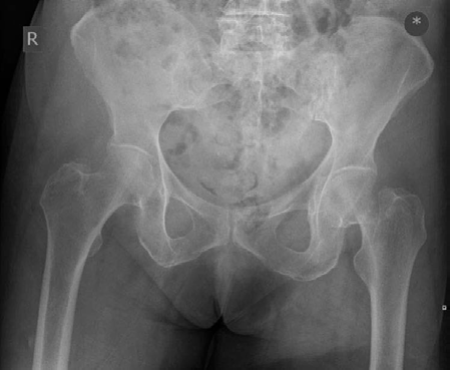

Orthopaedic oncology Structured oral examination question 5: Chondrosarcoma EXAMINER : This is a very fit and…